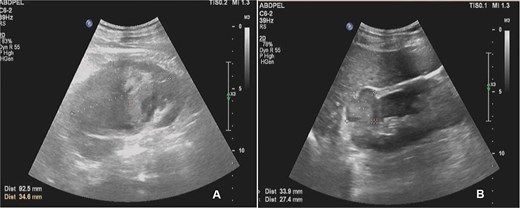

Abdominal ultrasound demonstrated bilateral renal masses and a left subcapsular renal hematoma (Fig. 1). Multiphasic contrast-enhanced computed tomography (CT) revealed multiple bilateral renal tumors with a left subcapsular hematoma, bilateral renal hilar lymphadenopathy, a right retroperitoneal nodule, a mass in the pancreatic uncinate process, and a right adrenal lesion (Fig. 2).

Abdominal ultrasound showing multiple solid masses in both kidneys and a subcapsular hematoma in the left kidney.